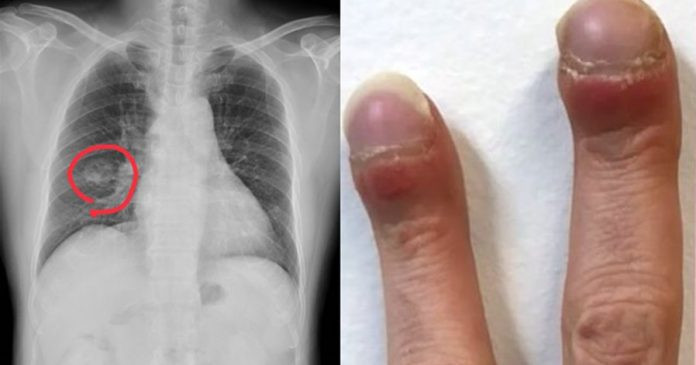

| Bác sĩ Hồng chia sẻ hình ảnh về trường hợp bệnh. |

Nhiều triệu chứng ung thư phổi dễ bị nhầm lẫn với các bệnh ít nghiêm trọng hơn. Tuy nhiên, có một số dấu hiệu nhận biết cần chú ý bên cạnh ho dai dẳng hoặc khó thở.